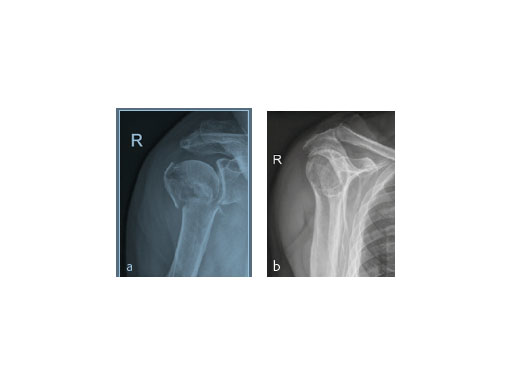

A 91-year-old female patient with osteoporosis had a dislocated 3-part proximalhumeral fracture in her right dominant arm (Fig 8).

The fracture was treated with PHILOS augmentation and healed in anatomical position (Fig 9).